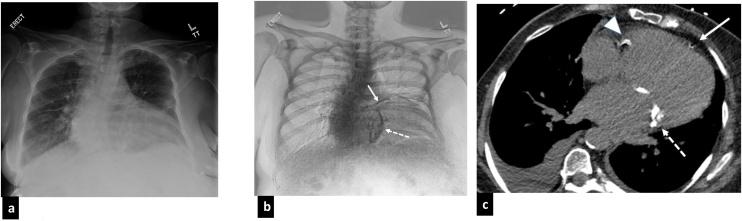

Recent advances in dual-energy imaging techniques, dual-energy subtraction radiography (DESR) and dual-energy CT (DECT), offer new and useful additional information to conventional imaging, thus improving assessment of cardiothoracic abnormalities. DESR facilitates detection and characterization of pulmonary nodules. Other advantages of DESR include better depiction of pleural, lung parenchymal, airway and chest wall abnormalities, detection of foreign bodies and indwelling devices, improved visualization of cardiac and coronary artery calcifications helping in risk stratification of coronary artery disease, and diagnosing conditions like constrictive pericarditis and valvular stenosis. Commercially available DECT approaches are classified into emission based (dual rotation/spin, dual source, rapid kilovoltage switching and split beam) and detector-based (dual layer) systems. DECT provide several specialized image reconstructions. Virtual non-contrast images (VNC) allow for radiation dose reduction by obviating need for true non contrast images, low energy virtual mono-energetic images (VMI) boost contrast enhancement and help in salvaging otherwise non-diagnostic vascular studies, high energy VMI reduce beam hardening artifacts from metallic hardware or dense contrast material, and iodine density images allow quantitative and qualitative assessment of enhancement/iodine distribution. The large amount of data generated by DECT can affect interpreting physician efficiency but also limit clinical adoption of the technology. Optimization of the existing workflow and streamlining the integration between post-processing software and picture archiving and communication system (PACS) is therefore warranted.

双能成像技术的最新进展,即双能减影X线摄影(DESR)和双能CT(DECT),为传统成像提供了新的有用的附加信息,从而改善了对心胸异常的评估。DESR有助于肺结节的检测和特征描述。DESR的其他优点包括能更好地显示胸膜、肺实质、气道和胸壁异常,检测异物和植入装置,改善心脏和冠状动脉钙化的可视化,有助于冠状动脉疾病的风险分层,以及诊断缩窄性心包炎和瓣膜狭窄等疾病。市售的DECT方法分为基于发射的(双旋转/自旋、双源、快速千伏切换和分束)和基于探测器的(双层)系统。DECT提供几种专门的图像重建。虚拟非增强图像(VNC)通过消除对真正非增强图像的需求来降低辐射剂量,低能量虚拟单能图像(VMI)增强对比度,有助于挽救原本无法诊断的血管研究,高能量VMI减少金属硬件或高密度对比剂引起的线束硬化伪影,碘密度图像允许对增强/碘分布进行定量和定性评估。DECT产生的大量数据可能会影响解读医生的效率,但也限制了该技术在临床上的应用。因此,有必要优化现有的工作流程,并简化后处理软件与图像存档和通信系统(PACS)之间的集成。